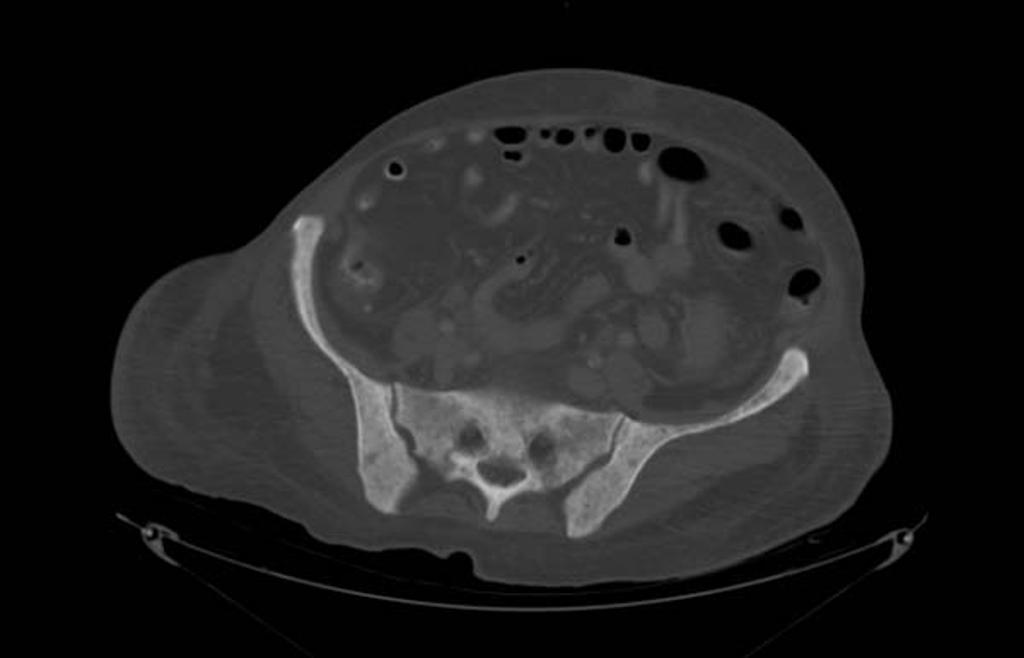

Rn ct

Rn ct 112 фотографий